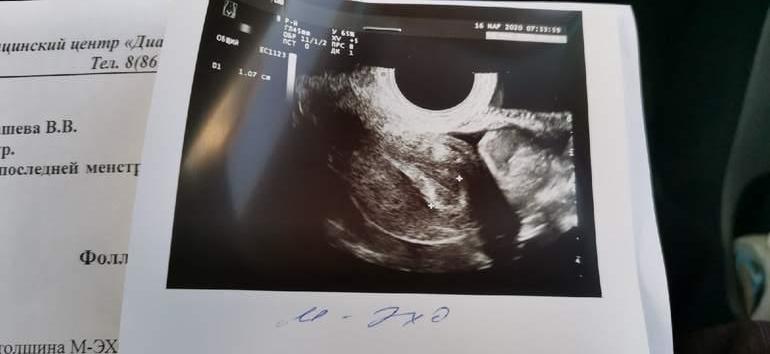

Напоминаю, что была у меня стимуляция клостом 100мг (2-5дц), потом укол ХГЧ 5000ед на 11дц и на 12дц была О.

Была на УЗИ на 9дц - ДФ 17мм слева и эндик 5,3мм

УЗИ СЕГОДНЯ (15ДЦ) ЭНННДИИИК 10,7мм 😍